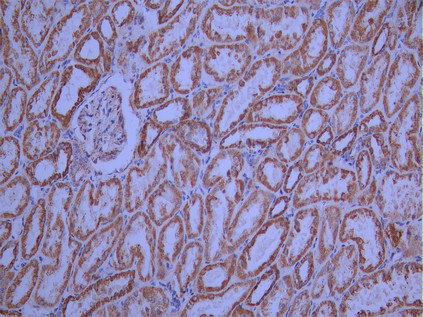

IHC image of CSB-RA208703A0HU diluted at 1:100 and staining in paraffin-embedded human kidney tissue performed on a Leica BondTM system. After dewaxing and hydration, antigen retrieval was mediated by high pressure in a citrate buffer (pH 6.0). Section was blocked with 10% normal goat serum 30min at RT. Then primary antibody (1% BSA) was incubated at 4°C overnight. The primary is detected by a Goat anti-rabbit polymer IgG labeled by HRP and visualized using 0.05% DAB.